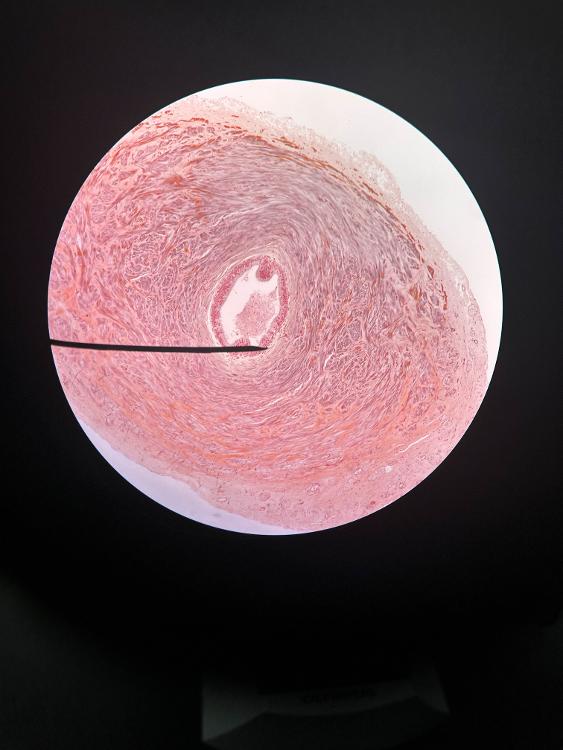

ductus deferens (10x)